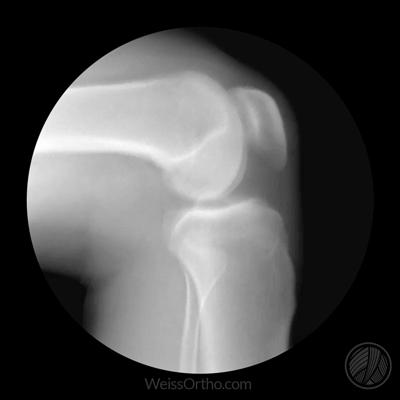

半月板是位于膝关节内股骨与胫骨关节之间非常重要的两块软骨结构,分别为内侧半月板以及外侧半月板,因为其形态大部分都是像月牙一样的形状,所以得名半月板,但是也有部分人群半月板是满月的,这种情况我们称之为盘状半月板或者是盘状软骨,多数都是外侧半月板,容易出现这种先天的解剖异常。

半月板和位于股骨远端,以及胫骨近端的关节软骨,共同构成膝关节内的缓冲系统,可以发生形态上的改变,比如在膝关节屈伸的过程当中,半月板可以发生厚薄以及宽窄的变化,可以更好的匹配膝关节的活动,增加膝关节的稳定性,另外在跑跳等运动过程当中,由于有了关节软骨和半月板的作用,才能承受冲击,这就相当于我们开车的减震系统,有了它们的存在,才能使我们的骨骼与骨骼之间不能直接硬碰硬。